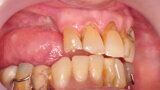

Osteonekroza występująca po zastosowaniu bisfosfonianów